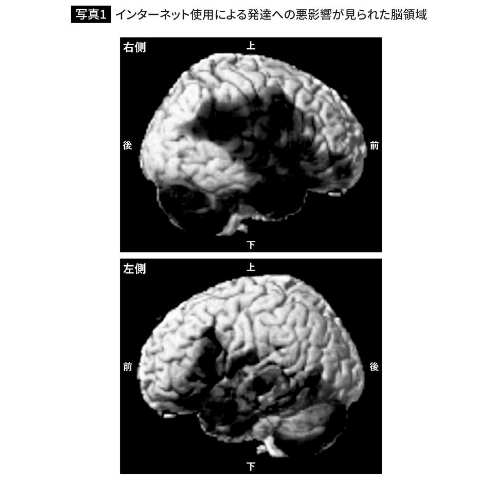

如今几乎人手一部或数部手机,而玩手机的人群也越来越低龄化,那么手机究竟对中小学生带来多严重的影响呢?根据近期日本专家追踪三年的研究结果显示,中学生入学得到手机后开始天天上网或者玩游戏,脑力将直接停滞在小学6年级水平不再发展。

·调查结果来自日本知名脑科专家川島隆太(参与多部关于脑力的游戏制作)监修,榊浩平原著的《智能手机究竟破坏大脑到何等程度?》,专家通过持续三年追踪那些经常玩手机游戏或者看视频、刷社媒的中小学生,平均年龄11岁的学生共计223人参与了调研,结果令人惊骇。

·调研结果显示,“每天通过手机泡在因特网的中小学生们,三年期间脑力完全没有发展,举个例子,如果学生在中学刚入学时就得到了手机并沉迷其中,三年后毕业时将不得不以小学6年级的脑力迎接中考。”